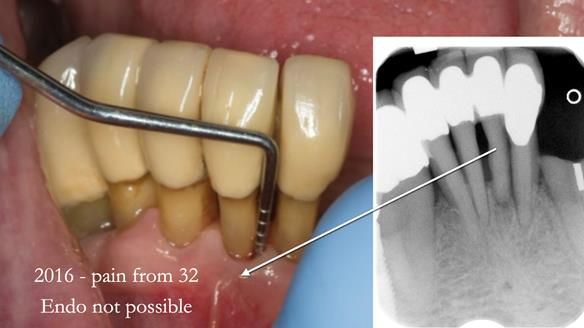

In 2016, Ken developed pain from tooth 32.

Endodontics was not possible.

The root was resected.

The tooth was already linked to 41 and 42,

and we were able to retain it

without compromising denture stability or retention.